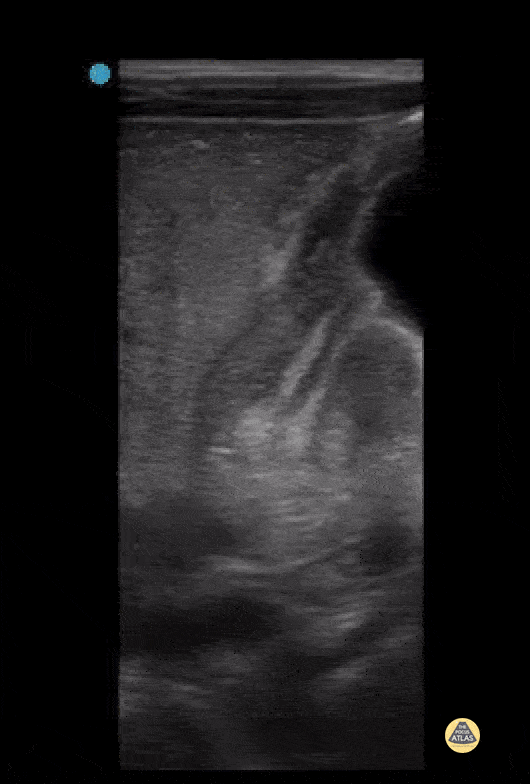

Peds-Gastrointestinal - Pyloric Stenosis - Antral Nipple Sign

3 week old with projectile vomiting, POCUS showed positive astral nipple sign which is a highly specific finding for pyloric stenosis - the redundant pyloric mucosa protrudes into the gastric antrum. The measurements show increased pyloric muscle thickness (>3mm) and increased pyloric longitudinal measurement (>15 - 17 mm) Measurements can be remembered using "Pi Rule" - Pyloric muscle thickness, i.e. diameĀ­ter of a single muscular wall on a transverse image >3 mm - Pyloric transverse diameter >14 mm - Pyloric longitudinal measurement >15 - 17 mm Contributed by: Dimitri Livshits DO, Ultrasound Fellow; Jane Belyavskaya MD, Ultrasound Fellow; Chris Hanuscin MD, Ultrasound Division Director (Kings County/SUNY Downstate)